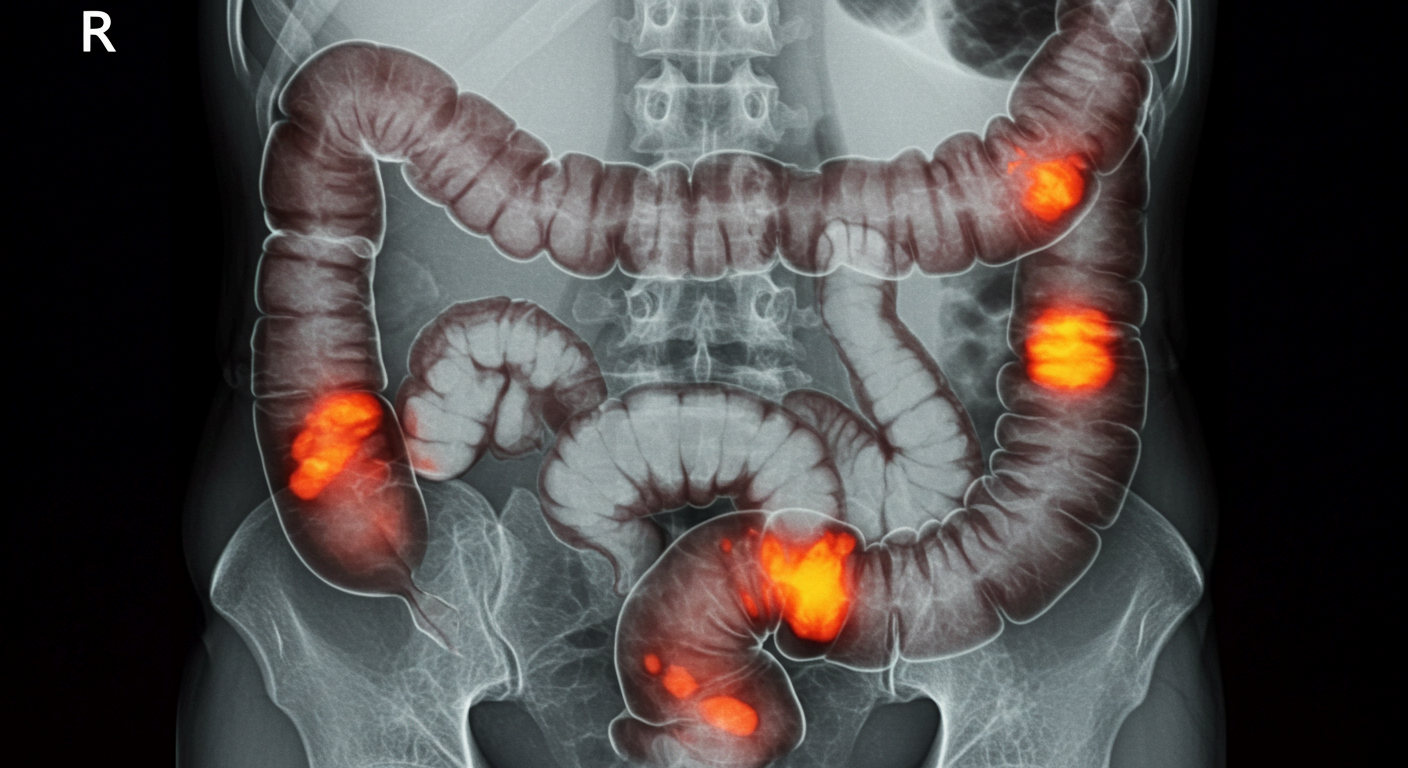

평소 배가 더부룩하고 통증이 반복된다면 단순 소화불량이 아닐 수 있습니다. 장폐색은 장 속 내용물이 흐르지 못하고 막히는 상태를 말하는데, 방치하면 장 괴사나 패혈증 같은 심각한 합병증으로 이어질 수 있습니다.

특히 장폐색 증상은 초기에는 단순 복통과 비슷해 놓치기 쉽지만, 빠르게 대응하지 않으면 생명을 위협할 수 있어 주의가 필요합니다. 이 글에서는 장폐색 증상, 원인, 치료 방법까지 한 번에 정리해 드리니 꼭 끝까지 확인해 보시길 바랍니다.

장폐색은 말 그대로 장이 막혀 소화물이 내려가지 못하는 질환입니다. 소장이나 대장 어느 부위에서나 발생할 수 있으며, 음식물·가스·체액이 쌓여 장이 팽창하면서 심한 복통과 구토를 유발합니다.

장폐색은 크게 기계적 장폐색(종양, 염증, 이물질 등 물리적으로 막힌 경우)과 마비성 장폐색(장 운동이 마비된 경우)으로 나눌 수 있습니다. 특히 기계적 장폐색은 즉각적인 수술이 필요한 경우가 많아 빠른 진단이 필수적입니다.